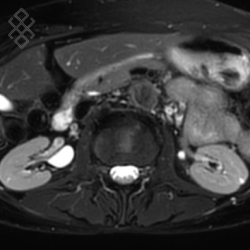

IRM des Reins / Artères rénales